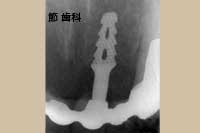

④ この症例は前歯用のブレード型チタンコートPOIインプラント を右上1本目の前歯部に埋入し、隣在する歯とブリッジ状に連結する事で欠損補綴を行ったものです。当時のブレード型POIインプラントは、“ベンダー”にて埋入部分と露出部分の角度設定を施し、無理のない角度で骨内へ埋入出来るようにしていました。